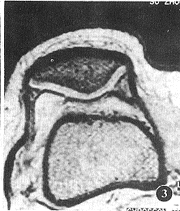

图2A,B MPR像,关节镜示髌软骨Ⅱ级退变损伤

图3 同图2,FFE-T1WI未能显示 软骨病变

2.2 3D-Volume-FFE T1WI矢状位原始图像及横断位MPR图像正常髌软 骨由表及里呈高、低、高信号的平行三层结构,表面光滑,底层钙化软骨层呈线状低信号分 隔软骨和软骨下骨质(图1B)。股骨滑车软骨呈与髌软骨类似的MRI表现(图1C),仅厚度略薄 ,其中10个滑 车面软骨均匀一致变薄,信号分层特点不明显,但表面仍光滑,关节镜证实为正常软骨面。 FFE T1WI关节软骨MRI表现类似3D-Volume-FFE T1WI,但信噪比稍差,本组5例髌上囊积 液用该序列扫描,软骨与液体界面不能区分。SE-T1WI关节软骨呈高于骨皮质而低于骨髓 的中等信号,信噪比差,信号分层特点不明显,软骨与关节液界面不能确定。各序列软骨损 伤 MRI分级与关节镜分级对照见表2~4(图2~4)。